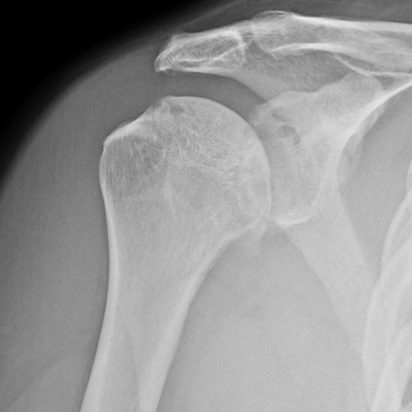

David had a shoulder hemiarthroplasty in November of 2023. Remembering from his previous experience shoulder surgery that he had lengthy recovery ahead, David was amazed how much better he felt in just 2 weeks after his surgery. Below David shares his recovery: